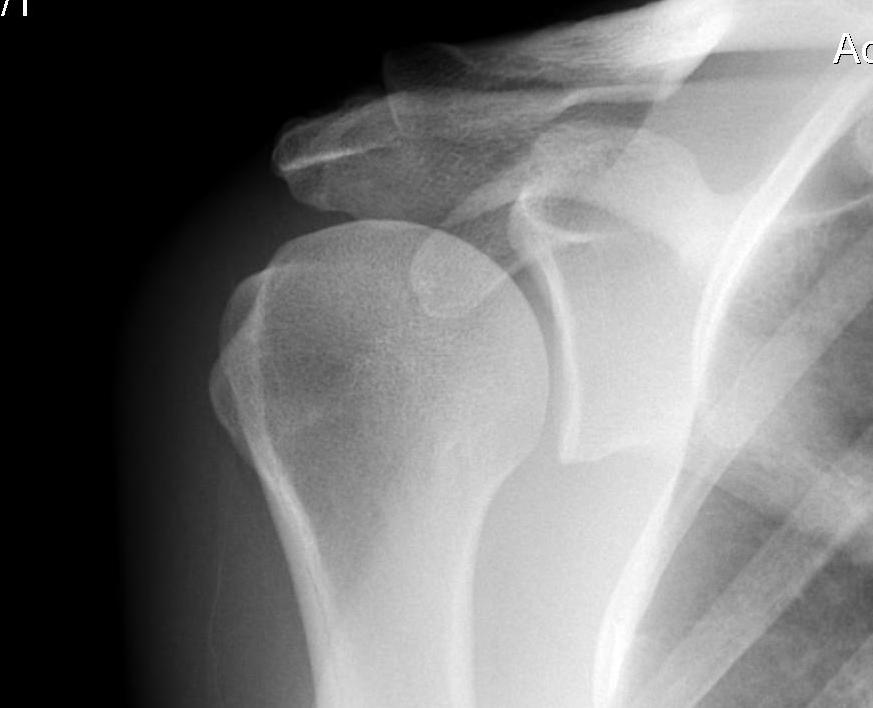

X-ray

| AP | Supraspinatus outlet view | Axillary lateral |

|---|---|---|

|

Sclerosis greater tuberosity / acromion Lateral Acromion spur |

Acromial morphology | Os acromiale |

Type III acromial spur associated with a full thickness rotator cuff tear